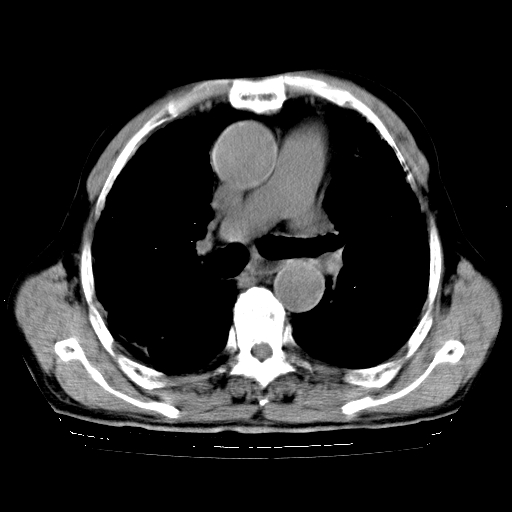

标题: CT25149:男,69岁,反复咳嗽、咳痰五年余,呼吸困难三天。 [打印本页]

男,69岁,反复咳嗽、咳痰五年余,呼吸困难三天。

慢支伴感染、肺气肿、肺心病

慢支伴感染、肺气肿、肺心病!支持!另:间质纤维化!

慢支伴感染、肺气肿、肺心病。双肺间质性改变(间质纤维化)。